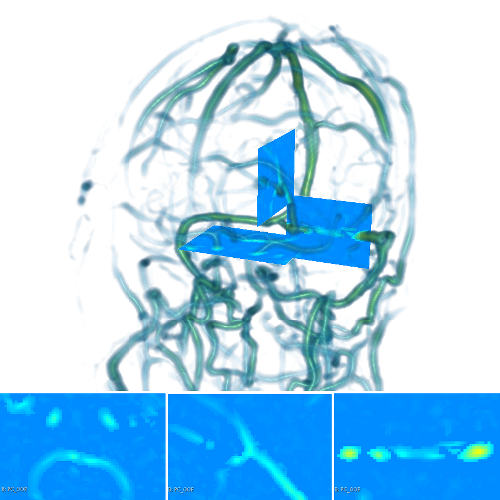

The scalar vesselness responses of both HCP and PC images are determined using the state-of-the-art Frangi filter (FFR) [8], and Optimally Oriented Flux (OOF) [12]. Also, the connected vesselness map (CVM) and the associated tensor field (TF) are synthesized for the same dataset using VTrails. The connectedness of the considered scalar maps is qualitatively assessed and the TF is inspected as proof of concept in section 3.1.

| Image | FFR | OOF | CVM | TF | |

| HCP |  |

|

|

|

|

| PC |  |

|

|

|

|

3.1 Connectedness of the Vesselness Map

Fig. 3 shows the connectedness of vessels recovered from state-of-the-art vascular enhancers and curvilinear ridge detectors FFR and OOF together with the proposed CVM for the synthetic HCP and the real PC images.

On the synthetic phantom, FFR shows a fragmented and rough vesselness response in correspondence of irregularly shaped sections of the structure. Also, the response at the bifurcation is not smoothly connected with the branches (triangular loop). Conversely, OOF recovers the phantom connectedness at the branch-point, and the vesselness response is consistent along the tortuous curvilinear section, however ghosting artifacts are observed as the shape of the phantom becomes irregular (C-like) or differs from a cylindrical tube. Also, close convoluted structures, which change scale rapidly in the HCP, produce inconsistent responses of OOF (fig. 3). CVM shows here a strongly connected vesselness response in correspondence of both regular and irregular tubular sections, with local maxima at structures’ mid-line. The connectedness of the structures is emphasized regardless the complexity of the shape, and it resolves spatially the tortuous curvilinear ‘kissing vessels’ without additional ghosting artifacts, despite the smooth profile.

Similar results are observed on the PC dataset: FFR has a poor connected response in the noisy and low-resolution image. Vessels are overall enhanced, however thin and fragmented structures remain disconnected. Overall, the vesselness response is not uniform within the noisy structures, where maximal values are often off-centred. A more consistent response is obtained from OOF, where the connectedness of vessels is improved. Maximal response is observed at the mid-line of vessels, however, noise rejection is poor. CVM strongly enhances here the vessel connectivity. The fragmented vessels of PC have a continuous and smooth response in CVM with higher values and a more defined profile. Large vessels shows solid connected regions with local maxima at mid-line as in OOF. Conversely from OOF, CVM shows improved noise rejection in the background.

The respective tensor fields (TF) synthesized on both HCP and PC show consistent features. The TF’s characteristics are in line with the connectedness of CVM: enhanced and connected vessels are associated with high anisotropy, whereas background areas show a predominant isotropic component.